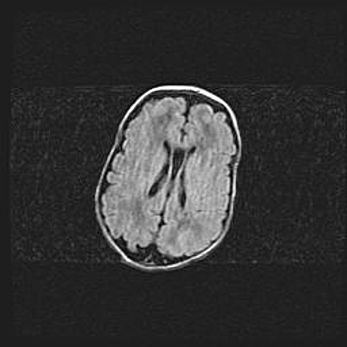

Лейкомаляция с кистозно-глиозной дегенерацией головного мозга.

Возраст: 2 месяца 25 дней

Вес: 6400 г

Окружность головы: 40 см

Срок гестации: 41 неделя

Лейкомаляцию относят к ишемически-гипоксическим повреждениям головного мозга, диагностируемым у новорожденных. При лейкомаляции в головном мозге обнаруживают очаги некроза, возникшие после тяжелой гипоксии и нарушения кровотока. В процессе морфогенеза очаги проходят три стадии: 1) развития некроза, 2) резорбции и 3) формирования глиозного рубца или кисты. Перивентрикулярная лейкомаляция (ПЛ) встречается примерно в 12% случаев среди новорожденных, обычно – у недоношенных детей, причем, частота ее зависит от массы, с которой младенец появился на свет. Наибольшее число малышей страдает лейкомаляцией, если масса при рождении 1500-2500 г.